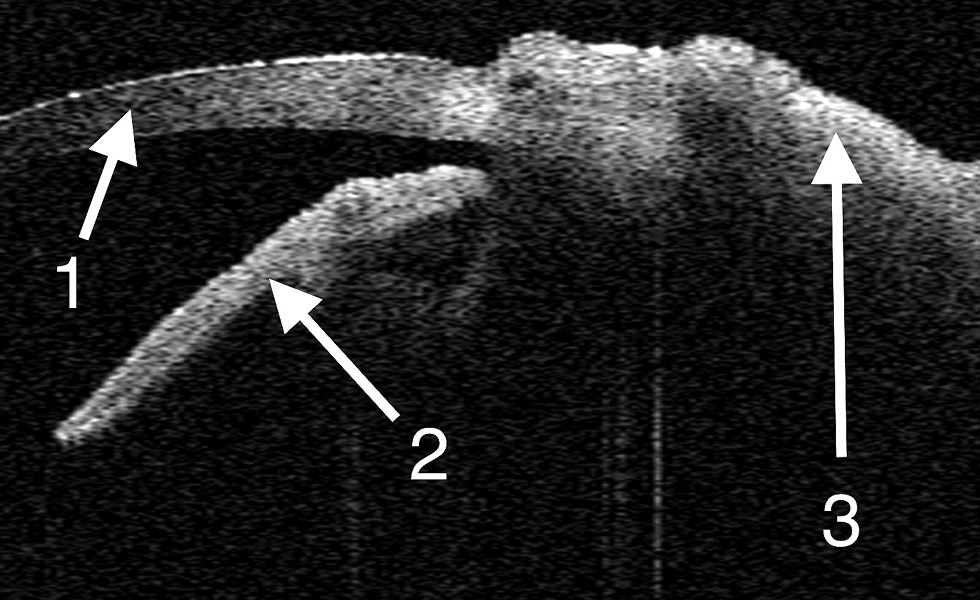

При динамическом наблюдении особенно тщательно следили за состоянием роговицы, пересаженных лоскутов конъюнктивы и обнажённого участка склеры. В раннем послеоперационном периоде клинически у всех животных отмечали отёк и гиперемию тканей конъюнктивы. Признаков токсикоаллергической реакции не наблюдали ни в одном из случаев. В зоне дефекта определяли плотную белесоватую ткань с бугристой поверхностью. По данным УБМ на 7-е сутки после операции в области аппликации клея и фиксации конъюнктивальных лоскутов визуализировали гиперэхогенную линейную пресклеральную структуру — это слой клеевой плёнки. Кроме того, выявляли локальное утолщение конъюнктивы со снижением эхогенности в зоне вмешательства (рис. 1). По данным ОКТ были получены изображения интактной роговицы и неравномерно утолщённой конъюнктивы в зоне хирургического вмешательства (рис. 2).

Рис. 1. Ультразвуковая биомикроскопия на 7-е сутки после операции. В проекции конъюнктивы гиперэхогенное линейное включение — слой клеевой плёнки, незначительное утолщение и снижение конъюнктивы (стрелка).

Fig. 1. Ultrasound biomicroscopy on Day 7 post-surgery. In the projection of the conjunctiva, a hyperechoic linear inclusion is visualized: a layer of adhesive film, with a slight thickening and reduction of the conjunctiva (arrow).